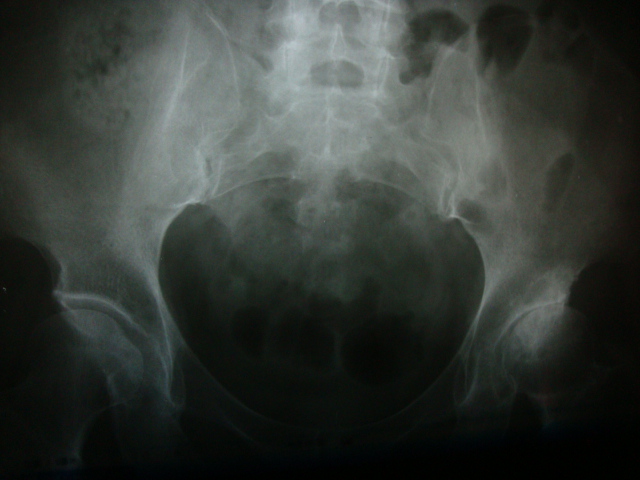

患者女58岁左腿跛行数月。

左侧髋关节间隙明显变窄,髋臼上缘硬化,左股骨头骨质未见明显异常,首先考虑左侧髋关节退变,可结合ct或mri检查看有否股骨头坏死。

成人髋臼发育不良 引起的退变

双侧髋臼发育不良继发退变,左侧无菌性坏死可疑。

左髋关节间隙明显变窄,髋臼上缘硬化。左股骨头可见斑点状密度减低区。双髋臼稍扁平。考虑双髋关节发育不良导致退变。建议mri排除左股骨头坏死

髋臼发育不良性骨关节病

左髋关节发育不良所致退行性变,股骨头缺血性坏死早期少有关节间隙的改变

左侧髋关节发育不良并退行性病变